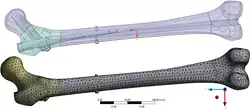

Vnitřní fixace - design hřebu pro femur

Vnitřní fixace - design hřebu pro femur -